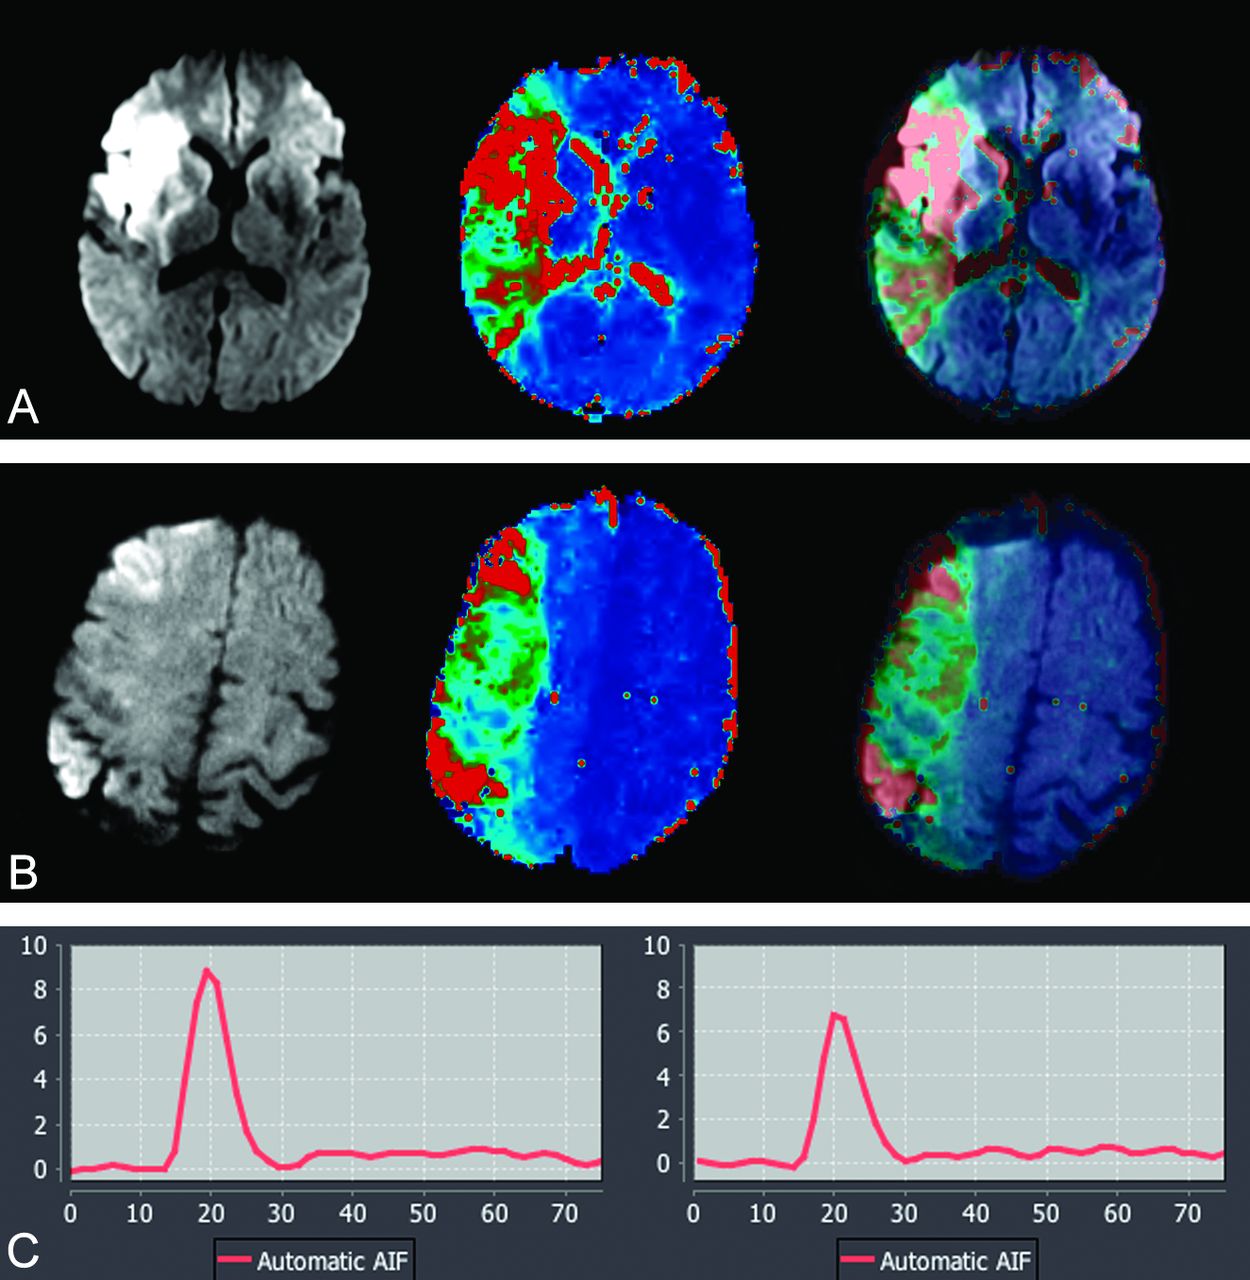

A, 62-year-old man with acute stroke; NIHSS score, 14. MR imaging was performed at 3T, 5 hours after the onset (from cohort group: 0.1 mmol/kg of gadolinium used for dynamic susceptibility contrast perfusion). B, 58-year-old man with acute stroke; NIHSS score, 16. MR imaging was performed at 3T, 3 hours after the onset (from study group: 0.05 mmol/kg gadolinium was used for dynamic susceptibility contrast perfusion). Serial DWI, Tmax, and superimposed DWI-Tmax demonstrate diagnostic image quality in both patients. A large perfusion-diffusion mismatch was identified with high confidence in both patients. The corresponding arterial input function curves are shown. There is approximately 24% lower arterial peak in half dose (6.7) compared with full dose (8.9). There is only small difference between the full width at half maximum of full dose (13) versus half dose (15).

DSC Perfusion

The mean ± SD of the volume of infarction on DWI and hypoperfusion with Tmax >6 seconds were 16.5 ± 7.6 (mL)/120 ± 48 (mL) for the full-dose group and 18 ± 9 (mL)/137 ± 70 (mL) for the half-dose group (P = .2). The mismatch ratios calculated automatically by the software demonstrated DWI-perfusion mismatch in all patients in both groups. DWI-perfusion mismatch was identified in 100% of the full-dose group and 90% of the half-dose group by both observers, with high confidence (r = 1).

There was no statistically significant difference in the SNR and background noise values between half- and full-dose groups (Table 3). When the baseline SNR of the initial phase of the perfusion study before arrival of contrast was evaluated, there was no significant difference (P = .6) between the mean baseline SNR of the full-dose (342 ± 101) and half-dose groups (330 ± 67), indicating an absence of significant recirculation effects. The maximum T2* signal drop values were higher in the full-dose group (P = .01). There was statistically significant higher AIF peak in the full-dose group (P = .002). There was however, no statistically significant difference between the FWHM of the AIF curves among the full-dose and half-dose groups (P = .1) (Table 3).